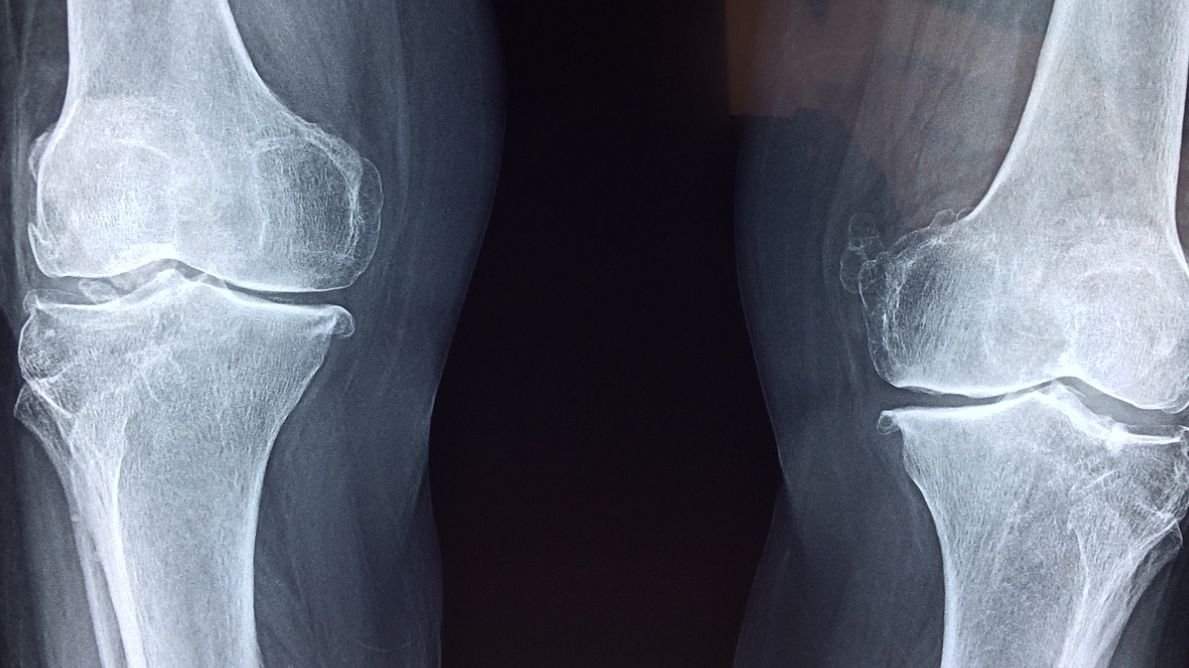

Podstawową funkcją osteoklastów jest resorpcja kości. To powolne wchłanianie składników mineralnych kości, które prowadzi do jej wymiany lub zaniku. W prawidłowo funkcjonującym organizmie jest to proces naturalny.Podstawową funkcją osteoklastów jest resorpcja kości. To powolne wchłanianie składników mineralnych kości, które prowadzi do jej wymiany lub zaniku. W prawidłowo funkcjonującym organizmie jest to proces naturalny.

Podstawową funkcją osteoklastów jest resorpcja kości. To powolne wchłanianie składników mineralnych kości, które prowadzi do jej wymiany lub zaniku. W prawidłowo funkcjonującym organizmie jest to proces naturalny. Dzięki niemu możliwa jest odnowa tkanki kostnej. Resorpcja kości jest procesem zapewniającym odpowiednie modelowanie kości i utrzymanie ich właściwej wytrzymałości mechanicznej. Na proces kostnienia składają się dwie zasadnicze przemiany: osteoklastogeneza i osteoblastogeneza. Równowaga jaka istnieje pomiędzy tymi procesami odpowiada za proces remodelacji kostnej.

Remodelacja tkanki kostnej obejmuje zarówno kość gąbczastą, jak i zbitą. Na drodze remodelacji każdego roku odnowieniu ulega około 10% kości szkieletu. Jest to możliwe dzięki wzajemnej interakcji dwóch rodzajów komórek kostnych: osteoklastów i osteoblastów, które współpracują ze sobą w miejscach na powierzchni kości zwanych jednostkami przebudowy kości.

Czynność komórek jest pobudzana przez parathormon, a hamowana przez kalcytoninę, pośrednio przez estrogeny (wydzielanie kalcytoniny przez komórki tarczycy jest stymulowane przez estrogeny). To dlatego zmniejszenie ich stężenia w wieku pomenopauzalnym prowadzi do zbyt dużej aktywności osteoklastów i w rezultacie osteoporozy. Na nasilenie czynności wpływają cytokiny wydzielane przez limfocyty T. Warto pamiętać, że w nadmiernej ilości prowadzą do osteoporozy.